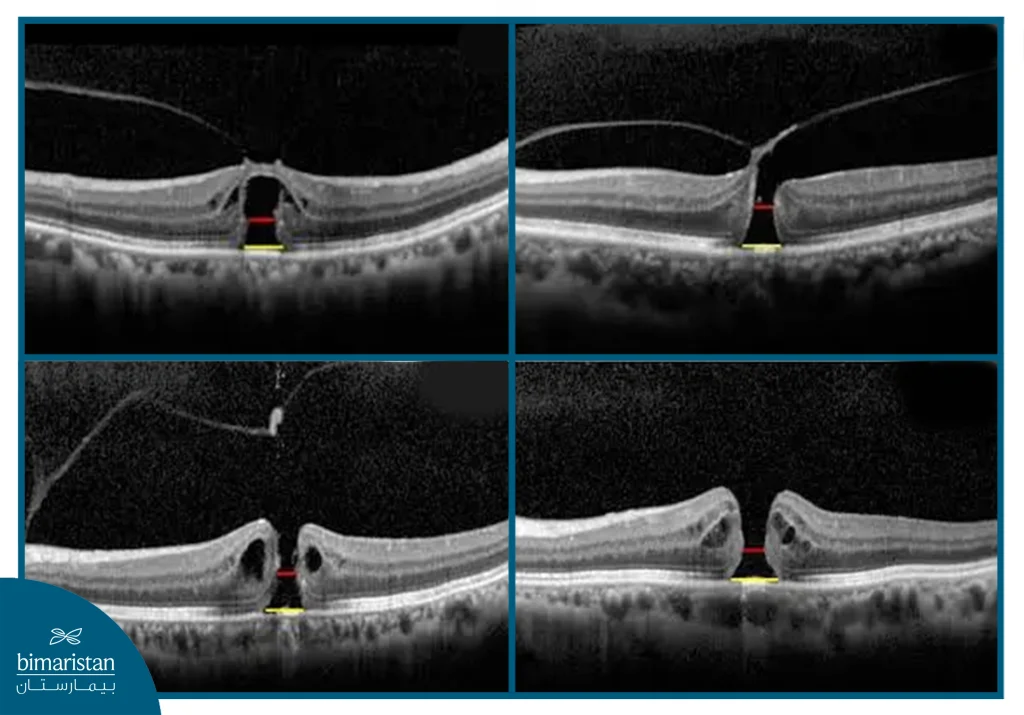

Optical coherence tomography (OCT) is the most important test for diagnosing a macular hole, as it uses light waves to create precise, high-resolution images of the different layers of the retina. This painless test allows the doctor to accurately identify the presence, depth, and stage of the hole, and helps distinguish it from other diseases that may present similar symptoms.